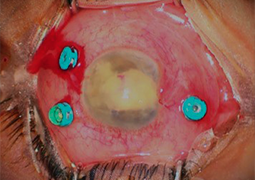

- Outcomes of Chandelier-Assisted Segmental Scleral Buckling Compared to Conventional Scleral Buckling for Primary Rhegmatogenous Retinal Detachment: A comparative retrospective study